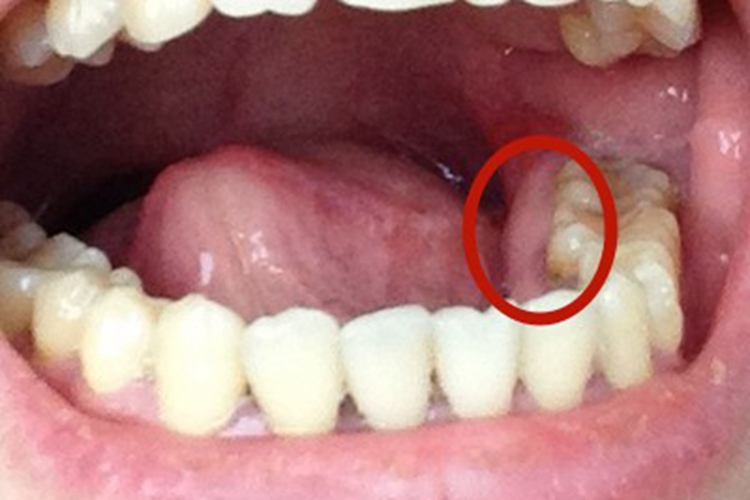

- 预防智齿冠周炎:智齿由于位置靠后,清洁难度大,容易积聚食物残渣和细菌,导致智齿冠周炎。拔除智齿可以有效避免这一问题的发生,维护口腔健康。

- 降低邻牙受损风险:智齿生长异常时,可能挤压或损伤邻牙,导致邻牙松动、龋坏,拔除后可以消除此隐患,保护邻牙健康。